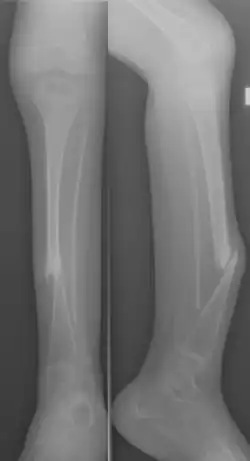

Primary CPT presents at birth or in infants as anterolateral bowing of the tibia. Bowing is observed as shortening of the corresponding leg, and is confirmed with X-ray imaging. It is commonly presented unilaterally, but can be bilateral.[1][8]

Congenital pseudarthrosis of the tibia (CPT) is a rare paediatric disease presenting with a bowing deformity of the tibia at birth or within the first decade of life.[1] It is most commonly associated with Neurofibromatosis type 1 (NF-1).[2] For children with CPT, pathological fracture of the tibia eventually occurs, resulting in persistent nonunion of the fracture site. If left untreated, leg deformities, joint stiffness, leg-length discrepancy and pain will persist.[3] Diagnosis is done clinically and through X-ray imaging, with numerous classifications based on the severity of bowing and presence of fracture or intraosseous lesion.[4]